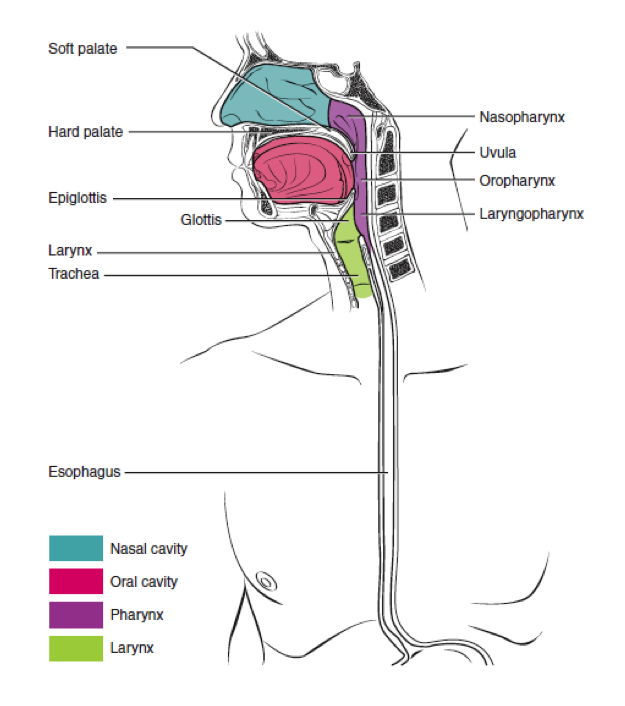

This page is under construction. For now, it is just a resource of the images found in the OpenStax Anatomy and Physiology Handbook. It wil slowly change into a revision tool. Each slide has a number. Use this to refer to the slide. When completed, it will have an unlabelled section, with labelled slides in parallel. On the unlabelled slides, write your answer and use the labelled slide to assess yourself. Keep track by also noting the number on each slide. Improvement at each attempt is important, more so than full marks on a first attempt.